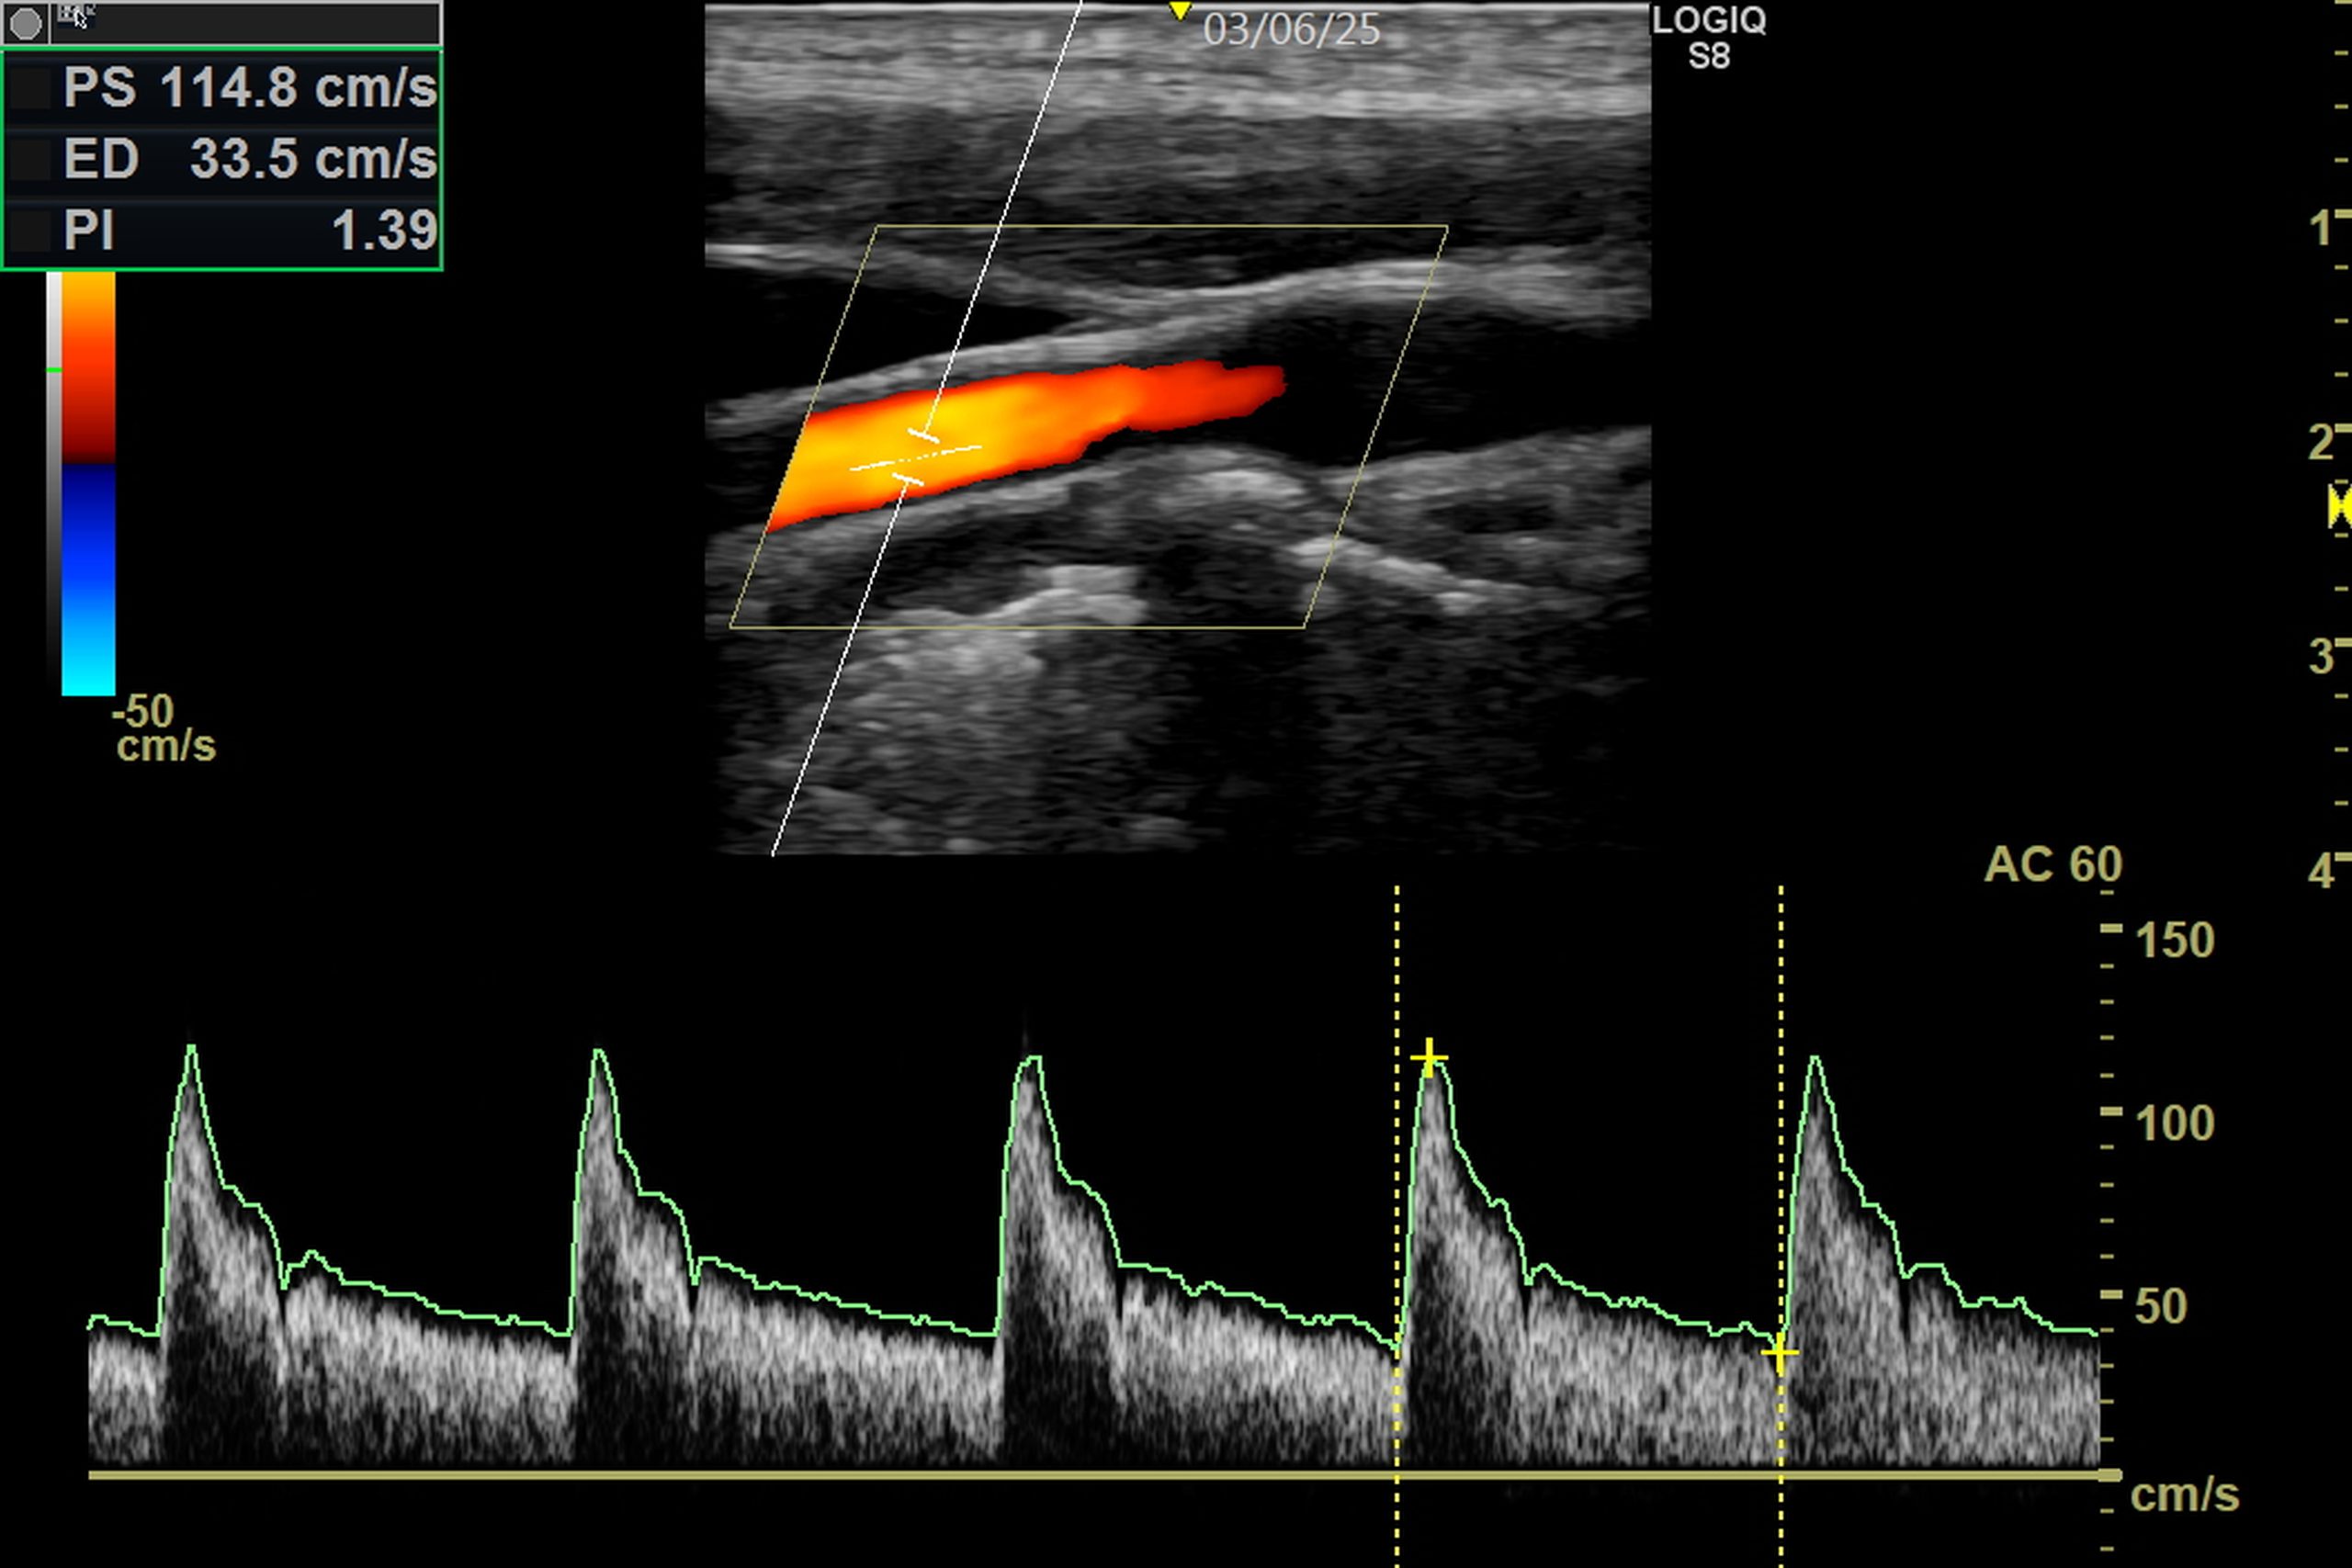

Ultraschall

Mit dem Ultraschall können wir die hirnversorgenen Gefäße untersuchen. Wir können so eine optimale Schlaganfall Vor- und Nachsorge anbieten.